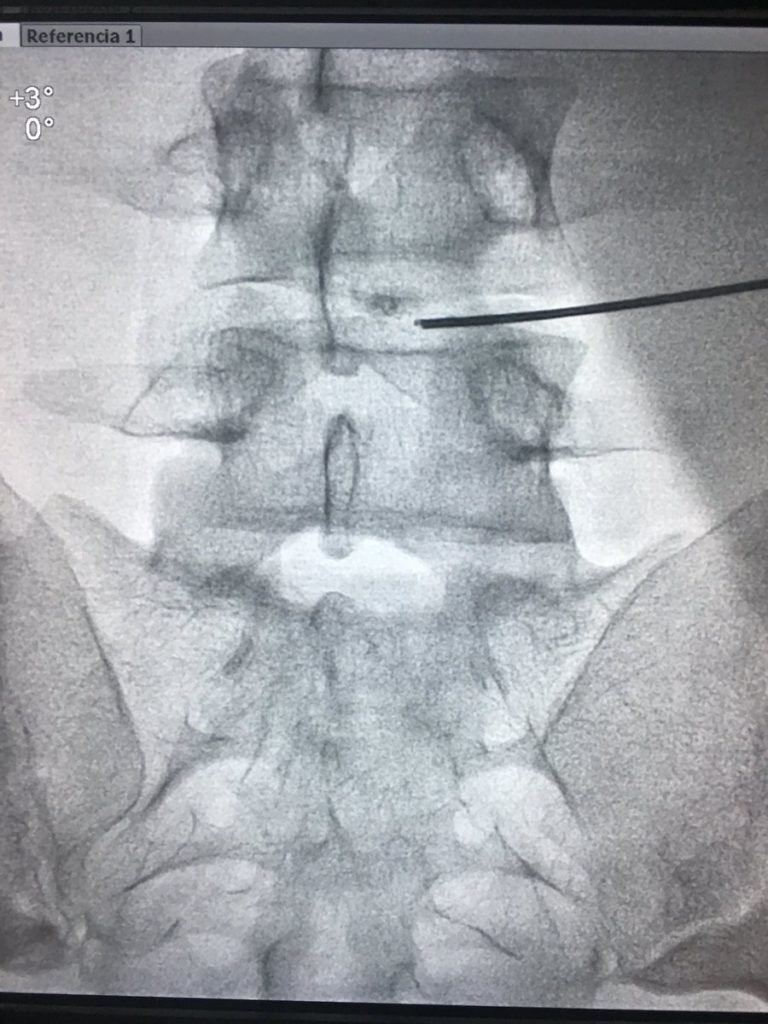

Τεχνική που εφαρμόζεται σε ασθενείς που πάσχουν από ισχιαλγία λόγω δισκοκήλης.

Προσθιοπίσθια ακτινοσκοπική προβολή υπό τοπική αναισθησία και ελαφρά Αναισθησιολογική «μέθη». Η βελόνα έγχυσης του φαρμάκου είναι μέσα στον ραγέντα πυρήνα του δίσκου έτοιμη για την έγχυση του φαρμάκου (“Discogel”)

Η τεχνική είναι ασφαλής για τις δισκοκήλες όπου δεν υπάρχει ρήξη του ινώδους δακτυλίου, γεγονός που εκτιμάται με ακρίβεια στη Μαγνητική τομογραφία. Σε πρόσφατες σχετικά δισκοκήλες, χωρίς εκφυλιστικά φαινόμενα των γύρω ιστών, τα ποσοστά επιτυχίας ξεπερνούν το 80 %.